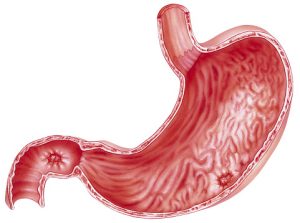

Frequent stomach upset and nausea? Could be a stomach ulcer, also known as a peptic ulcer , an open sore that can develop in the lining of your esophagus, stomach, or small intestine. How to get rid of ulcers or find ulcer pain relief? You first need to pinpoint the cause and then consider some home remedies for ulcers to help relieve your symptoms.

Frequent stomach upset and nausea? Could be a stomach ulcer, also known as a peptic ulcer , an open sore that can develop in the lining of your esophagus, stomach, or small intestine. How to get rid of ulcers or find ulcer pain relief? You first need to pinpoint the cause and then consider some home remedies for ulcers to help relieve your symptoms.

Why do stomach ulcers give people so much grief? They’re an open, painful wound. Bacteria weaken the stomach’s protective coating, so the acid gets through to the sensitive tissues lining the digestive system. The bacteria and acid work to irritate this lining, causing sores or ulcers.